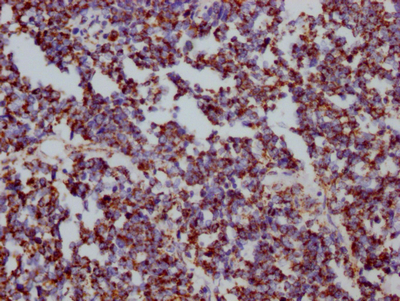

ApplicationELISA, WB, IHC, IP; Recommended dilution: WB:1:500-1:5000, IHC:1:50-1:200, IP:1:200-1:1000